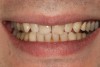

A 34-year-old male patient with no medical issues presented to the office with the chief complaint of a failing crown on tooth No. 12. The patient was also unhappy with his bite and the appearance of his teeth (Figure 1 and Figure 2).

The dentofacial examination revealed a low smile line with no incisor display when the lips were in repose. The anterior teeth were chipped and worn, and their overall color was darkened. The buccal corridors were deficient, and the failing crown on tooth No. 12 was visible in a full smile.

(1.) Preoperative smile photograph.

Figure 1